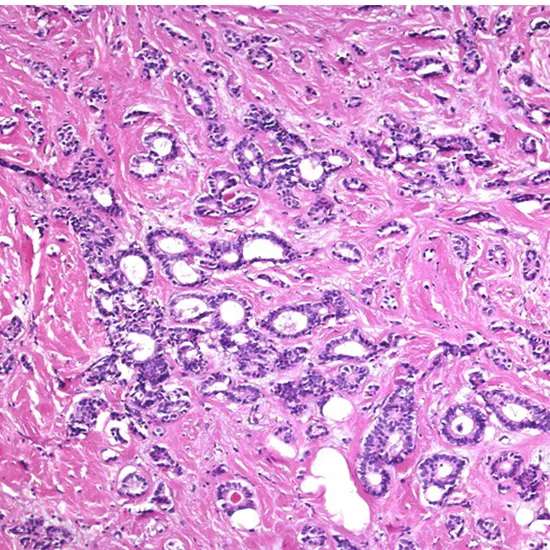

The histologic highlights of tubular carcinoma are the multiplication of well-differentiated organs or tubules, orchestrated in a tumultuous and frequently outspread design, with organs expanding unpredictably into adjoining sinewy stroma and fat tissue.

Tubular carcinoma may be a subtype of intrusive ductal carcinoma of the breast. More seldom, tubular carcinomas may emerge within the pancreas or kidney. Most tubular carcinomas start within the drain duct of the breast and spread to sound tissue around it.

Tubular carcinoma may be a sort of obtrusive ductal carcinoma where all the cancer cells see tube-shaped beneath a magnifying lens. Tubular carcinoma is uncommon and more often than not forceful. Typically the tumors are little and do not develop exceptionally quickly.

Tubular carcinoma could be a sort of IDC that creates within the drain conduits of the breast. The tumors tend to be little, as a rule, 1 centimeter or less in distance across. Tubular carcinoma gets its title from the tiny, tube-shaped structures that make up the tumors.